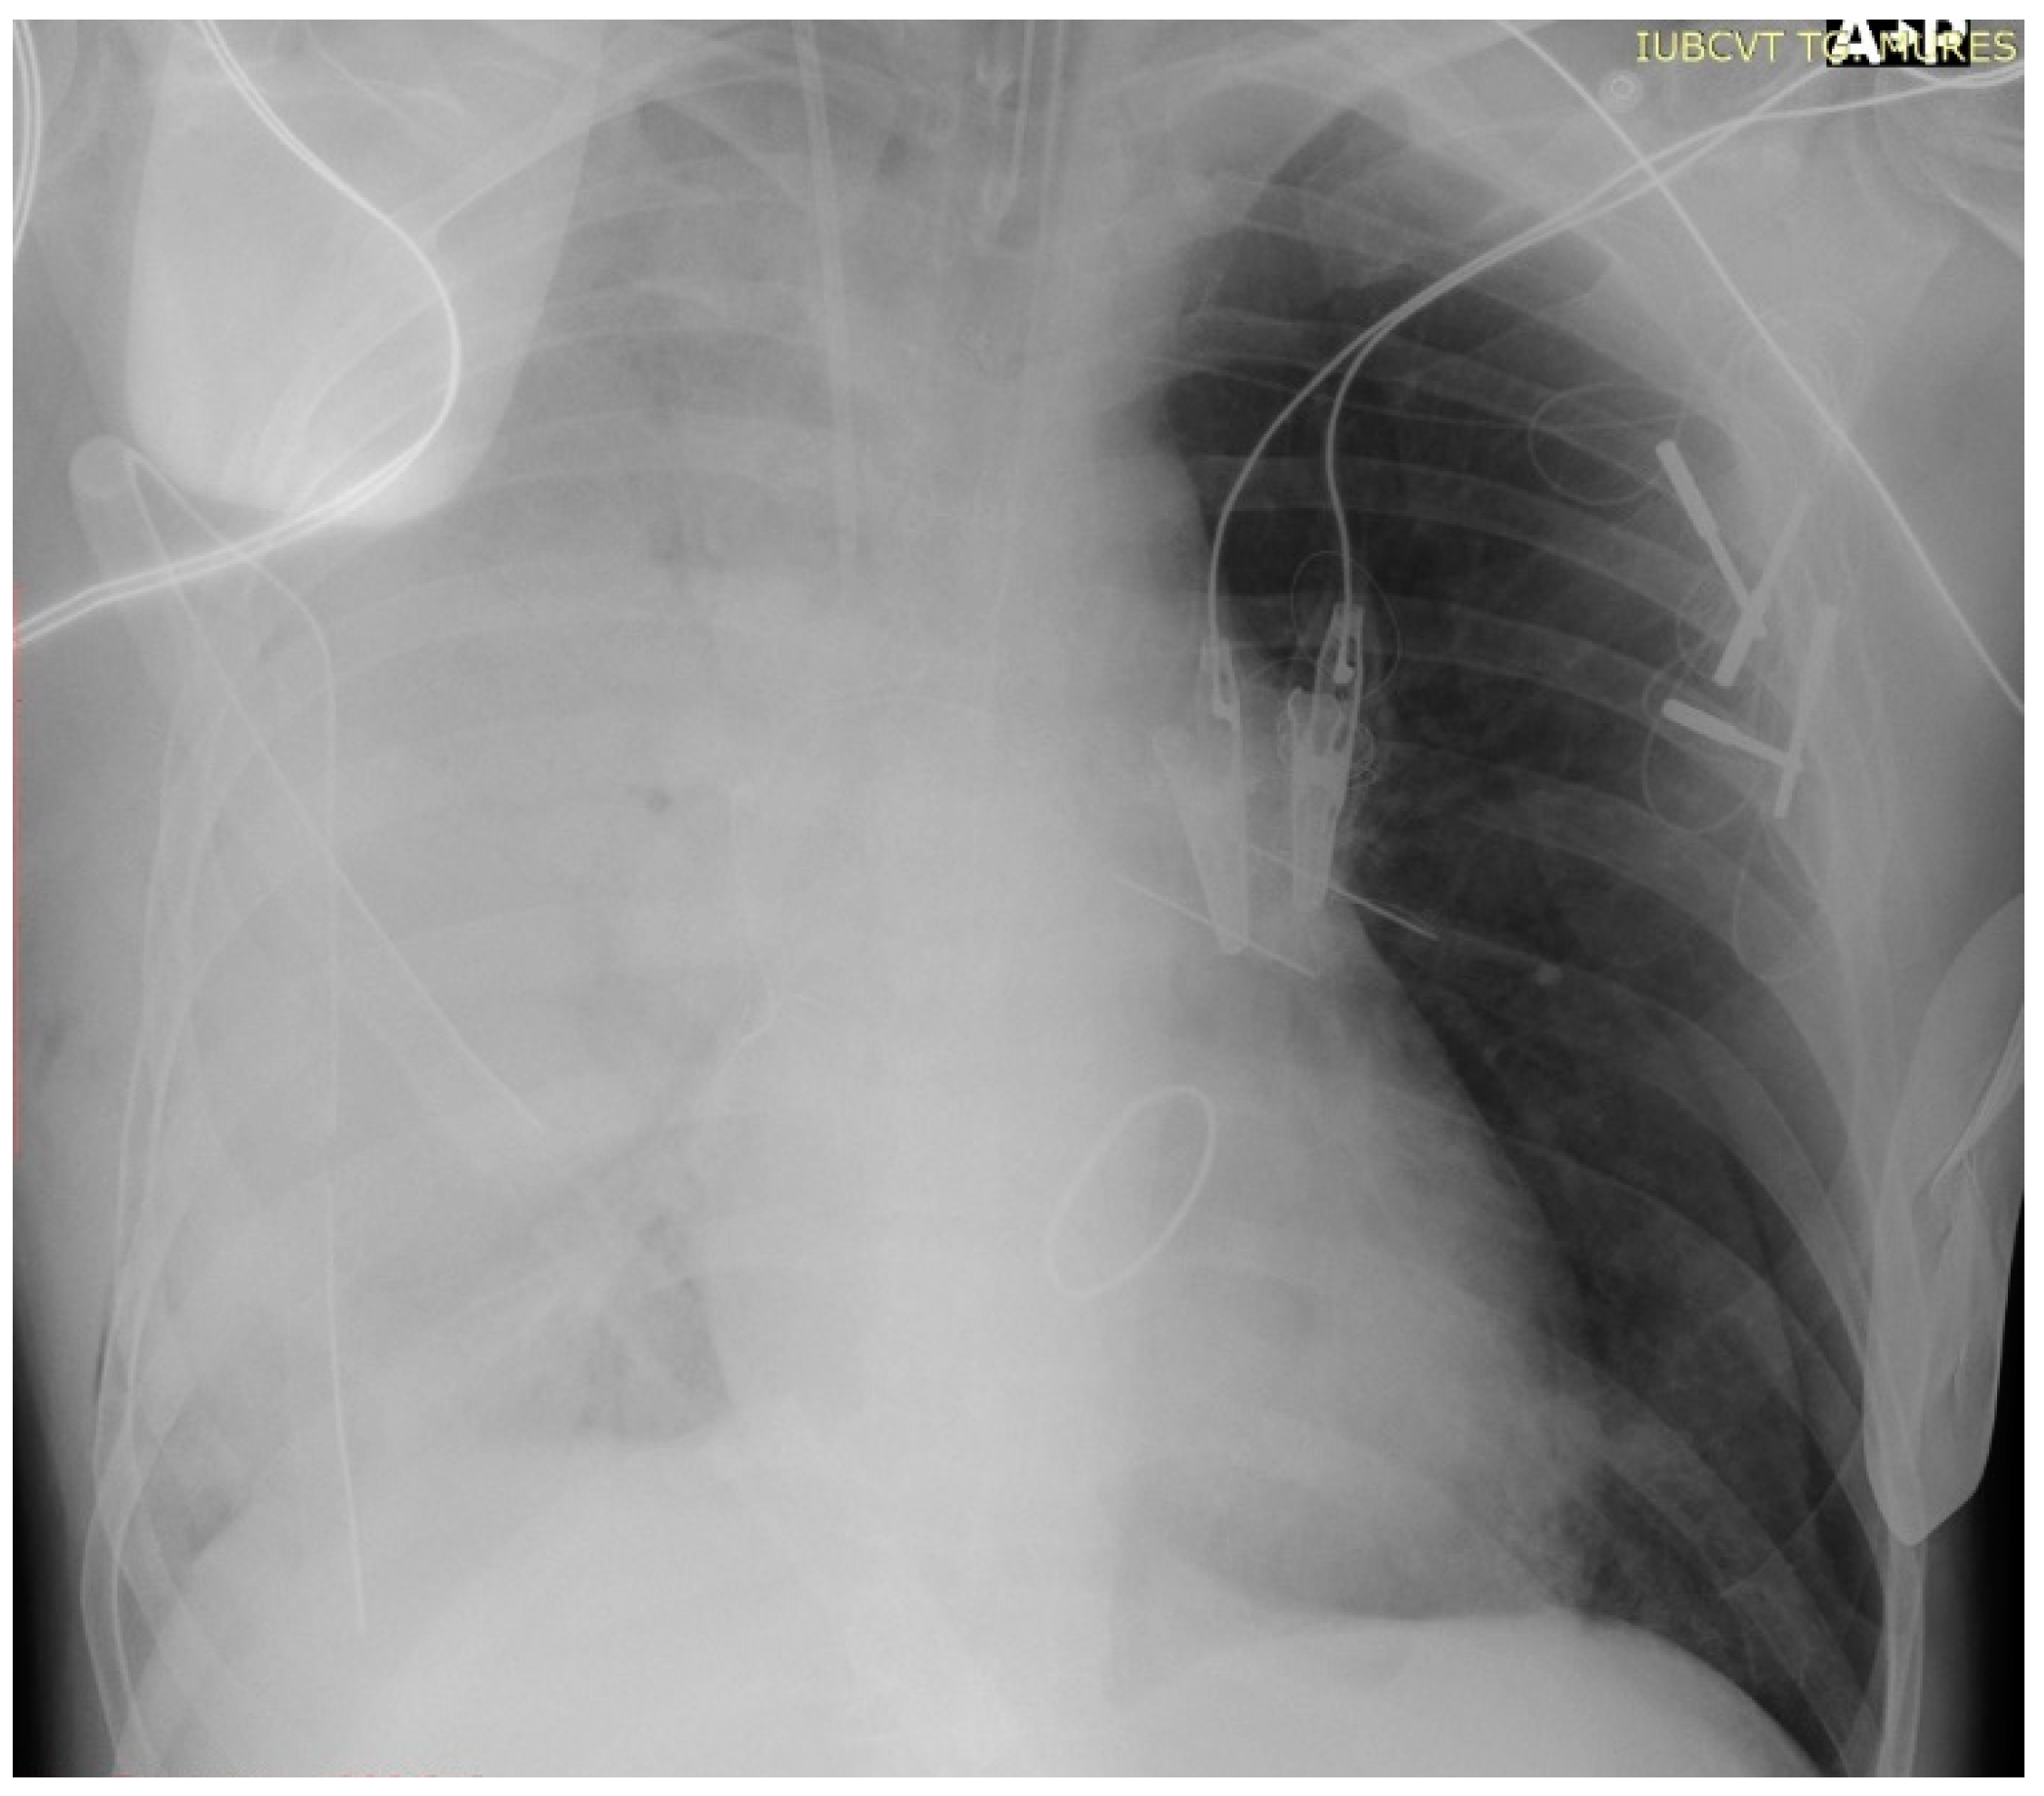

| Postoperative evolution | Right after Intensive Care Unit (ICU) admission, hypoxia abruptly developed, and serous discharge was aspirated through the endotracheal tube. The thoracic X-ray performed revealed dense alveolar opacities on the entire right hemithorax, confirming the diagnosis of unilateral pulmonary edema. | |

| Day 1 | The patient developed a left pneumothorax, confirmed by thoracic X-ray, worsening respiratory parameters, therefore requiring the insertion of a drainage tube. A thoracic X-ray after drainage confirmed the correct positioning of the tube and the complete expansion of the left lung. | |